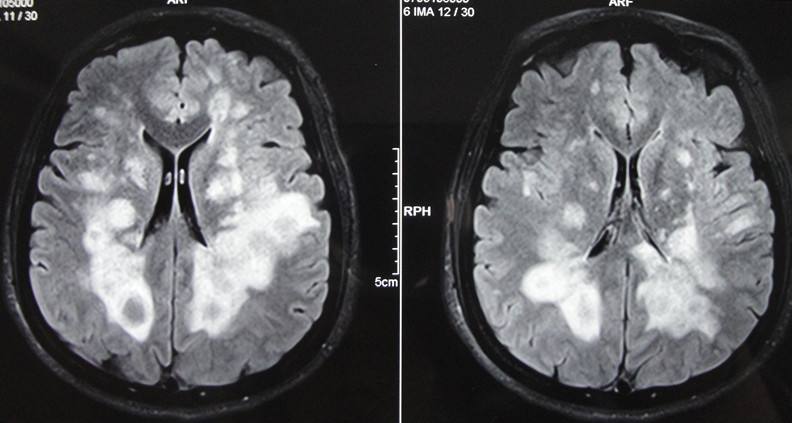

患者,男,李XX,41歲,家住本市,該患于入院前2年,無明顯誘因出現(xiàn)右側肢活動不靈,表現(xiàn)為走路時腿拖拽,伴有言語不利,尚可與人交談,在“吉林大學第一醫(yī)院二部”行頭部MRI及腰椎穿刺檢查后診斷為“脫髓鞘病”,治療后好轉出院,20天前患者癥狀加重,并伴有左側肢活動不靈,癥狀無緩解,未予任何治療來我院就診,病程中患者有視物雙影,飲食、睡眠尚可,尿便正常。查體:體溫36.5℃,脈搏71次/分,呼吸18次/分,血壓140/80mmHg,神志清楚,言語不利,查體合作,計算力、記憶力、定向力、理解力、判斷力正常,雙側額紋對稱,雙側瞳孔等大同圓,直徑約3.0mm,對光反射靈敏,雙眼各向運動正常,無眼球震顫,無鼻唇溝變淺,伸舌居中,懸雍垂居中,雙側咽反射靈敏,右側肢體肌力3級,左側肢體肌力4級,肌張力增高,膝腱反射亢進,雙側Babinski征(+),頸無抵抗 ,雙側Kernig征(-),昂伯士征(+),雙側肢體深、淺感覺未見異常,雙肺呼吸音清,心率71次/分,節(jié)律規(guī)整,各瓣膜聽診區(qū)未聞及雜音,腹平軟,無壓痛,肝脾肋下未觸及,雙下肢無浮腫。入院后行頭部、頸椎、胸椎MRI:脫髓鞘病病史: 雙側側腦室后角、下角旁、放射冠及半卵圓中心、胼胝體見片狀及團塊狀異常信號影,T1WI呈低信號,T2WI及FLAIR呈高信號;各腦室、腦池大小形態(tài)未見明顯異常,中線結構居中,矢狀面掃描示垂體大小形態(tài)正常。彌散成像腦質未見明顯異常高信號影。頸椎生理曲度變直,部分椎體邊緣骨質增生。C3/4、C4/5、C5/6間盤向后方局限性突入,硬膜囊前緣受壓。黃韌帶未見明顯增厚。頸髓未見明顯異常信號影。 胸椎生理曲度尚可,椎體骨質結構完整。各胸椎間盤未見明顯突出或膨出,黃韌帶無增厚。約T2、5、12椎體水平脊髓內(nèi)見條片狀長T2信號影。心電圖示:竇性心律,心率71次/分,大致正常心電圖。此次考慮患者脫髓鞘病復發(fā),經(jīng)過吉大一院劉群教授會診后,給予激素大劑量沖擊治療,病程中激素逐漸減量,經(jīng)過一個療程的治療,患者癥狀較前明顯好轉,肢體活動較前靈活,患者滿意的出了院。